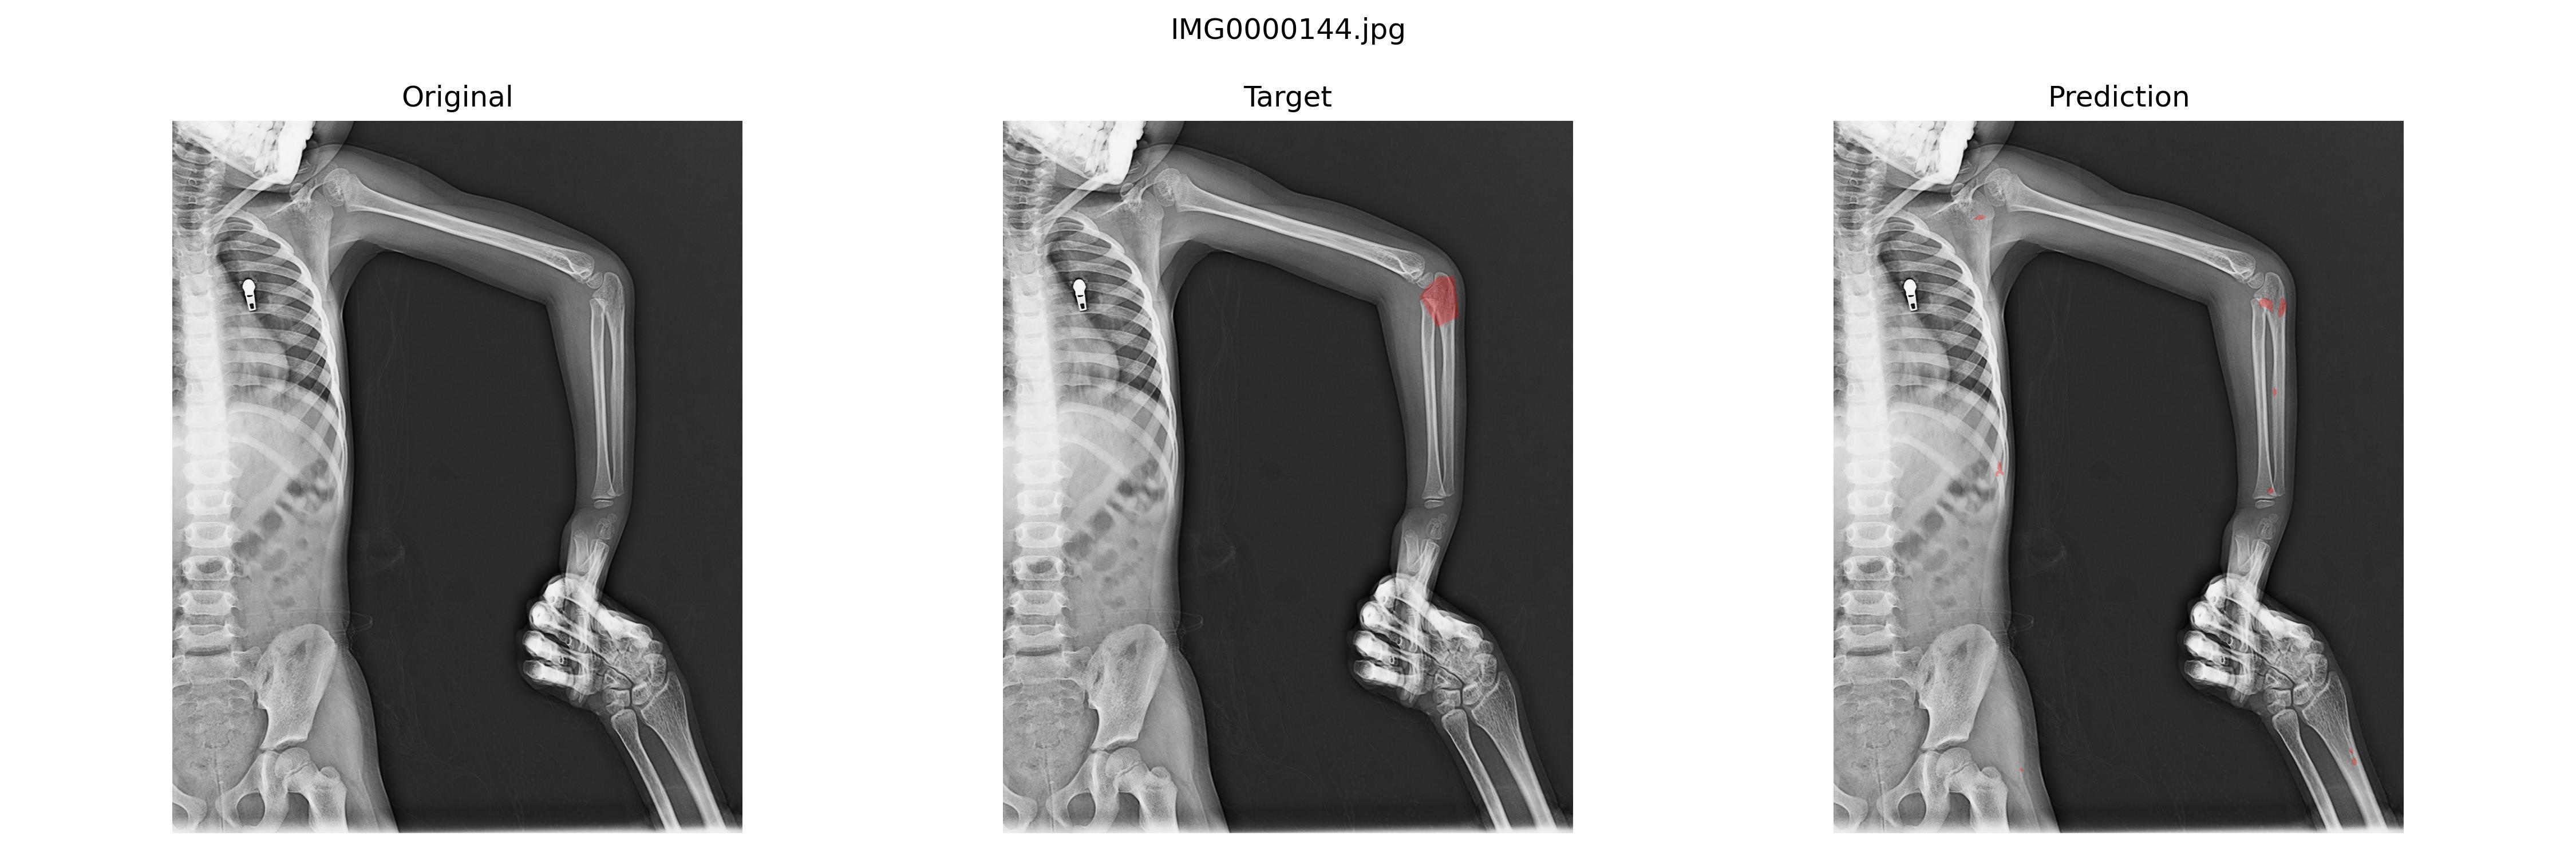

好的结果

不好的结果

最后结果并不是很好,并且换了U-net以及加权交叉熵损失、Dice损失之类的之后也一样,我认为和这个数据集的标注逻辑有关。骨折的地方就那个断面,周围标注可大可小,这种应该比较适合bbox标注做目标检测。